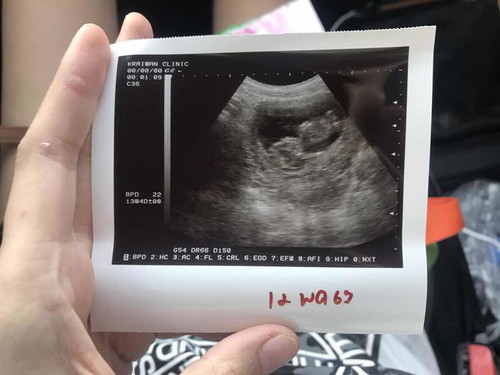

บ้านนี้กำหนดคลอด 2 พย.จ้าาา อันนี้รูปตอนตัวเล็กได้ 12 วีค ตอนนี้ 16วีคแล้ว รออาทิตย์หน้าจะไปซาวด์ดูเพศละค่ะ ลุ้นๆว่าจะยอมให้ดูมั้ย

15+4 ค่ะ กำหนดคลอด 10 พ.ย. บ้านนี้ได้ลูกสาวสมใจค่ะ ปล.ภาพ ultrasound ตอน 12 weeks ค่ะ